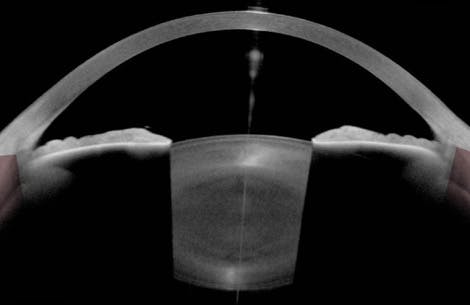

On examination, the patient’s IOP is 17 mm Hg OU. The angles are open (Figure 1). Mild superior thinning of the optic nerve is observed in the right eye, and asymmetric cupping (0.7 OD and 0.5 OS) is evident (Figure 2). Humphrey visual field testing (Carl Zeiss Meditec) shows inferior arcuate defects that are greater in the right versus left eye, in keeping with the optic nerve changes (Figure 3). OCT imaging of the optic nerves is suspicious for superior and inferior thinning bilaterally, but the findings are confounded by a split bundle artifact due to blood vessel anatomy in each eye (Figure 4).

COVID-19 has been associated with acute angle closure attacks due to prone positioning, hyponatremia, or swelling of the ciliary body, but these case reports all involved patients with shallow chambers. In this case, anterior segment OCT imaging shows a deep chamber. I therefore think asymptomatic, intermittent angle closure is highly unlikely. COVID-19 has also been reported in association with a number of retinal diseases that can cause visual field defects. These include acute macular neuroretinopathy, vein and artery occlusions, and neuro-ophthalmic disease. The patient’s nerves do not appear to be pale. Nor do the visual field defects respect a vertical midline.